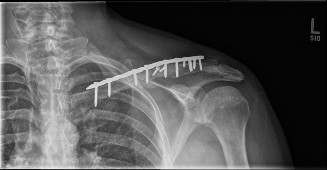

Implant Selection

Surgeons must choose between superior and anteroinferior plating, as well as between pre-contoured locking plates, reconstruction plates, and intramedullary devices. Pre-contoured locking plates offer superior biomechanical stability in comminuted fractures and osteoporotic bone. Superior plating provides a biomechanically advantageous tension band construct against the inferior pull of the arm, but carries a higher risk of hardware prominence. Anteroinferior plating utilizes longer screws in the anterior-to-posterior plane, directs drills away from the subclavian vessels, and generally results in less hardware irritation, though it may be more technically challenging to contour in specific fracture patterns.

Plate Application and Fixation

Once provisional reduction is achieved, the selected plate is applied. If a superior plate is chosen, it is positioned on the superior surface of the clavicle. Pre-contoured plates often require minor adjustments using bending irons to perfectly match the patient's unique anatomy. At least three bicortical screws, providing a minimum of six cortices of purchase, must be placed on each side of the fracture.

Drilling must be performed with extreme caution. The drill should be directed carefully, and an oscillating drill attachment or drill stops should be used to prevent plunging through the far cortex and injuring the underlying subclavian vessels or brachial plexus. The use of a blunt retractor or a periosteal elevator placed inferior to the clavicle can provide a physical barrier during drilling and screw measurement.

In comminuted fractures where anatomic reduction of intermediate fragments is impossible or requires excessive soft tissue stripping, bridge plating is the technique of choice. The plate is secured to the main medial and lateral fragments, spanning the comminuted zone to maintain length, alignment, and rotation while preserving the fracture hematoma.